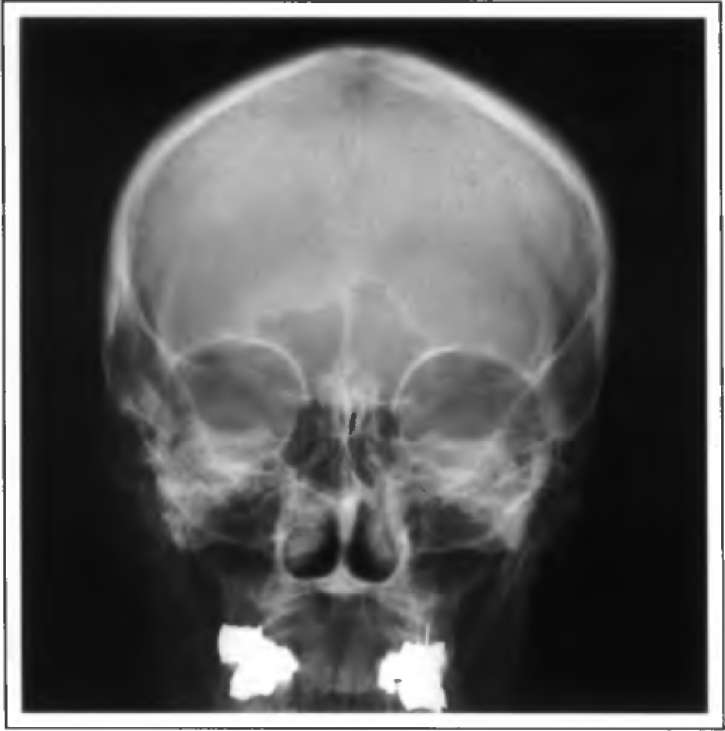

Рентгеновский снимок (рис. 1) в основном позволяет видеть составляющие части скелета таким образом, что могут быть определены переломы, смещения суставов или аномалии костей и связок. Технология применения рентгеновских лучей улучшилась в течение последних десятилетий, что привело к улучшению качества изображений и к сокращению необходимого для экспозиции времени. Теперь многие рентгеновские снимки получают цифровым методом. Метод радиографии является обязательным во многих случаях, например в хирургии, травматологии и пульмонологии, где необходима высокая контрастность изображений.

Рис 1. Рентгеновское изображение черепа (передне-задний вид) Рис. 2. Ультразвуковое изображение матки человека с трехмесячным эмбрионом

Рентгеновское изображение черепа Ультразвуковое изображение матки человека с трехмесячным эмбрионом